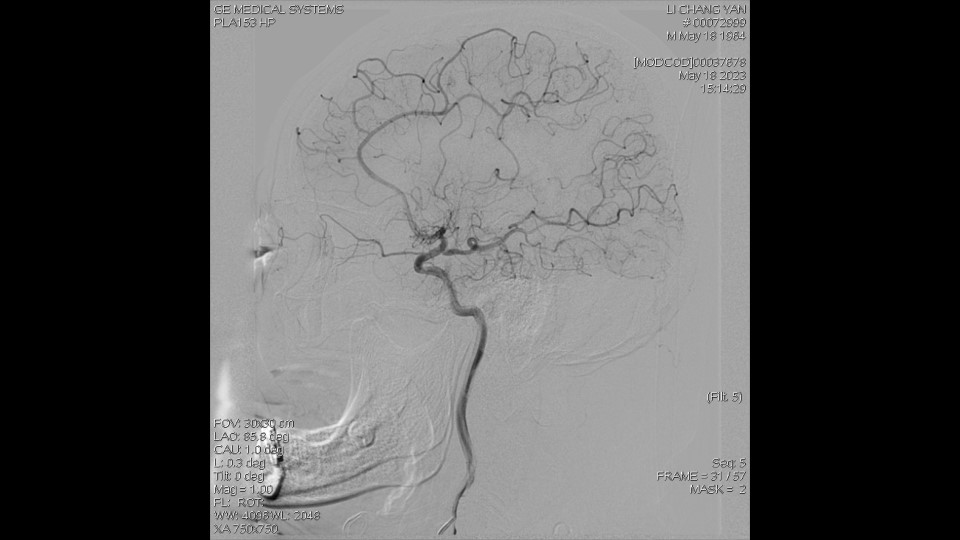

DSA显示:右侧MCA闭塞,依靠颅底软膜支、大脑前动脉代偿。